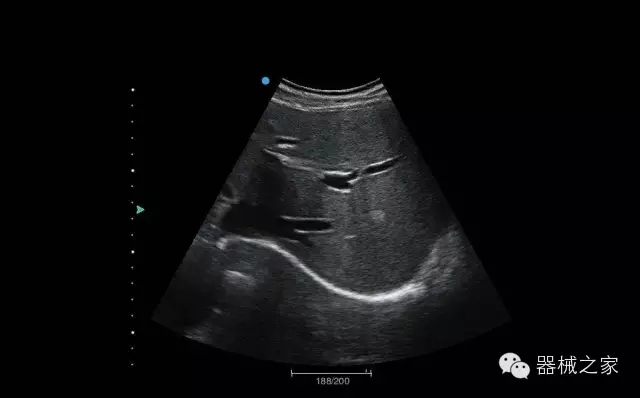

頸動(dòng)脈頻譜